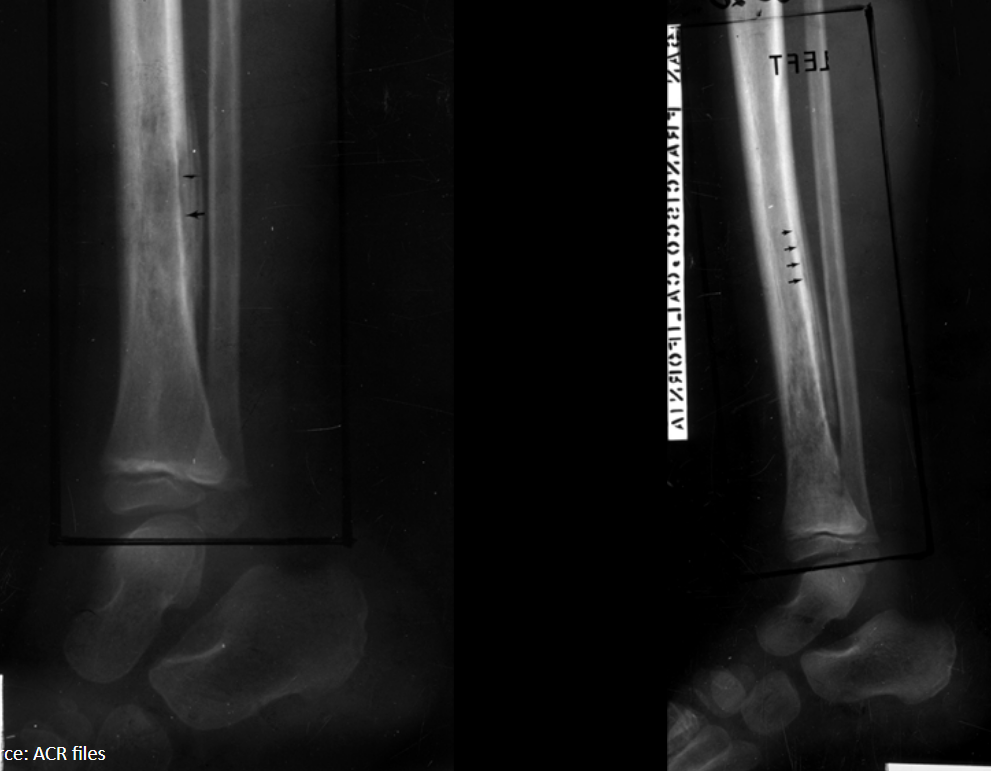

What periosteal reaction is present?

What is the differential diagnosis?

Laminated periosteal reaction (aggressive)

1. Osteomyelitis

2. Ewing sarcoma

3. Osteosarcoma

4. Lymphoma

diaphyseal lesion in immature skeleton